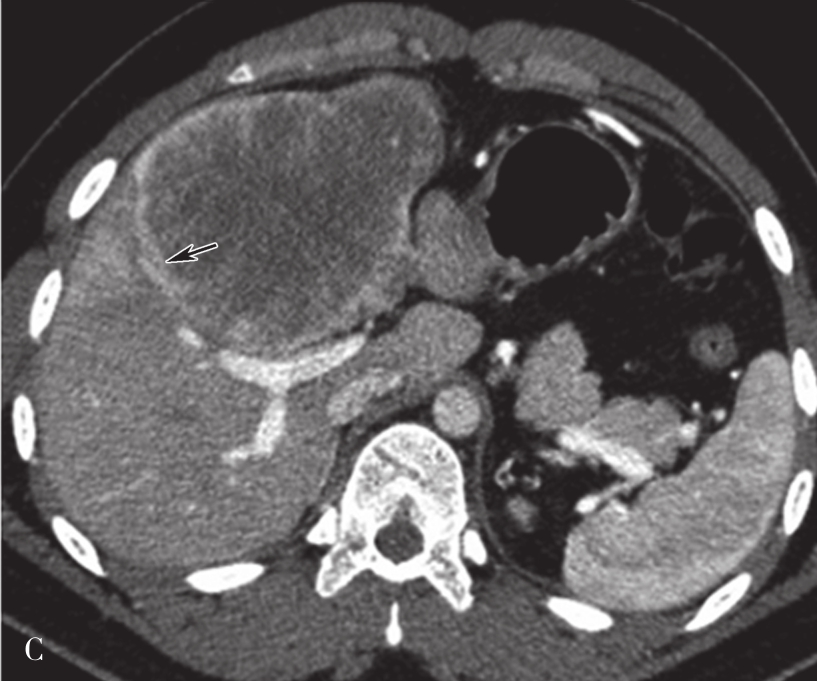

(1)肝脏大小和形态:

肝脏内的脂肪浸润及肝硬化再生结节使得肝脏体积增大,中、晚期肝硬化由于纤维组织增生又使得肝脏体积缩小,以肝裂增宽为主,胆囊窝扩大,肝脏表面呈波浪状改变。通常肝右叶缩小明显,而尾状叶及左叶则可出现代偿性的增大(图5-21-37)。

图5-21-37 CT增强扫描门静脉期图像

可见肝脏形态异常,肝裂增宽,肝叶比例失调,肝脏体积缩小,肝包膜增厚,肝脏边缘呈波浪状改变,门静脉主干管径增宽,直径约1.8cm。脾脏体积明显增大,脾静脉增粗,同时可见食管胃底静脉曲张(箭头),肝周、脾周可见弧形液性密度影

(2)肝脏密度:

肝硬化产生的纤维化、再生结节使得密度增高,肝细胞坏死及脂肪浸润使肝组织密度减低,局部脂肪组织浸润可出现局灶性的密度减低区。

(3)继发性改变:

包括门静脉高压所引起的脾肿大,腹水和食管胃底静脉曲张等。